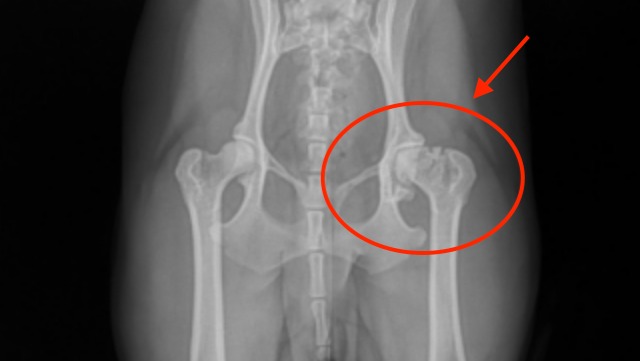

I rushed her to the emergency vet, where they took x-rays and discovered that poor Winnie's degenerative joint disease has progressed from moderate to severe.

A FHO is a surgical procedure that aims to restore pain-free mobility to a diseased or damaged hip by removing the head and neck of the femur - AKA they are gonna take off part of Winnie's bone!!

This part!